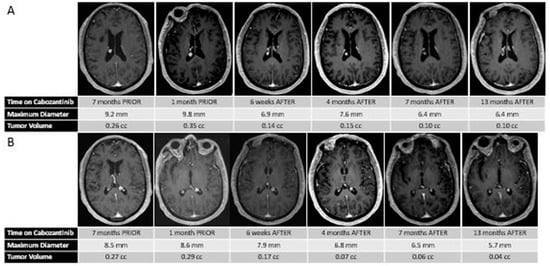

At age 70, five years after initial presentation, he presented with headaches, and an MRI scan of the brain revealed a left posterior frontal parafalcine lesion measuring 2 × 1.5 × 2.5 cm, along with two stable intraventricular meningiomas (measuring approximately 8.5 and 9.2 mm each). Interval brain MRI performed 2.5 months later, at the time of transfer to our center, revealed that the left parafalcine mass had increased in size to 3.5 × 3.4 × 2.4 cm, with moderate mass effect on the motor strip, with the two intraventricular putative meningiomas stable in size. Given the patient’s progressive weakness and lesion size, he underwent resection of the left posterior frontal parafalcine mass, and pathology confirmed metastatic thyroid carcinoma consistent with his known primary. He underwent post-operative stereotactic radiosurgery to the surgical cavity and continued observation was recommended for the putative stable meningiomas. Subsequent restaging studies revealed progressive metastatic cancer, with an increase in the size and number of metastatic pulmonary nodules, nodal progression in the neck, and enlarging osseous metastases. His two-month post-treatment brain MRI revealed no evidence of progression of the disease within the surgical cavity and the continued stability of the two intraventricular meningiomas. He was started on systemic therapy with cabozantinib 60 mg PO daily for his metastatic thyroid cancer, which was dose-reduced 6 weeks later to 40 mg PO daily due to modest fatigue. Interval follow-up brain MRI performed 8 weeks following treatment of the brain metastasis and 6 weeks post-cabozantinib demonstrated no radiographic recurrence at the surgical bed, but an unexpected and dramatic reduction in size and volume of the intracranial meningiomas (60% and 40% volumetric reduction) (see Figure 1). This response was sustained at an interval brain MRI performed for the surveillance of brain metastasis approximately 3 months on cabozantinib and continued until his most recent follow-up MRI performed approximately 1 year after starting therapy.

Figure 1.

(A) Sequential MR images demonstrating the changes in size and volume of the right putative intraventricular meningioma before and after treatment with cabozantinib. (B) Sequential MR images demonstrating the changes in size and volume of the left putative intraventricular meningioma before and after treatment with cabozantinib.